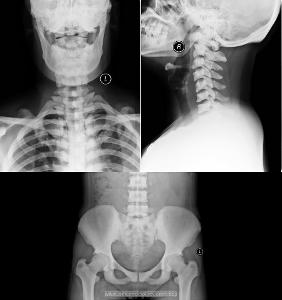

氟骨症(fluorosis of bone)是指长期摄入过量氟化物引起氟中毒并累及骨组织的一种慢性侵袭性全身性骨病。氟中毒累及牙齿称氟斑牙。1901年,Eaqer最早报道氟斑牙,1932年丹麦的Motlev和Gudijonsson命名为“氟中毒”(fluorosis),并认为本病伴有骨硬化。

۞ 氟骨症的影像学表现